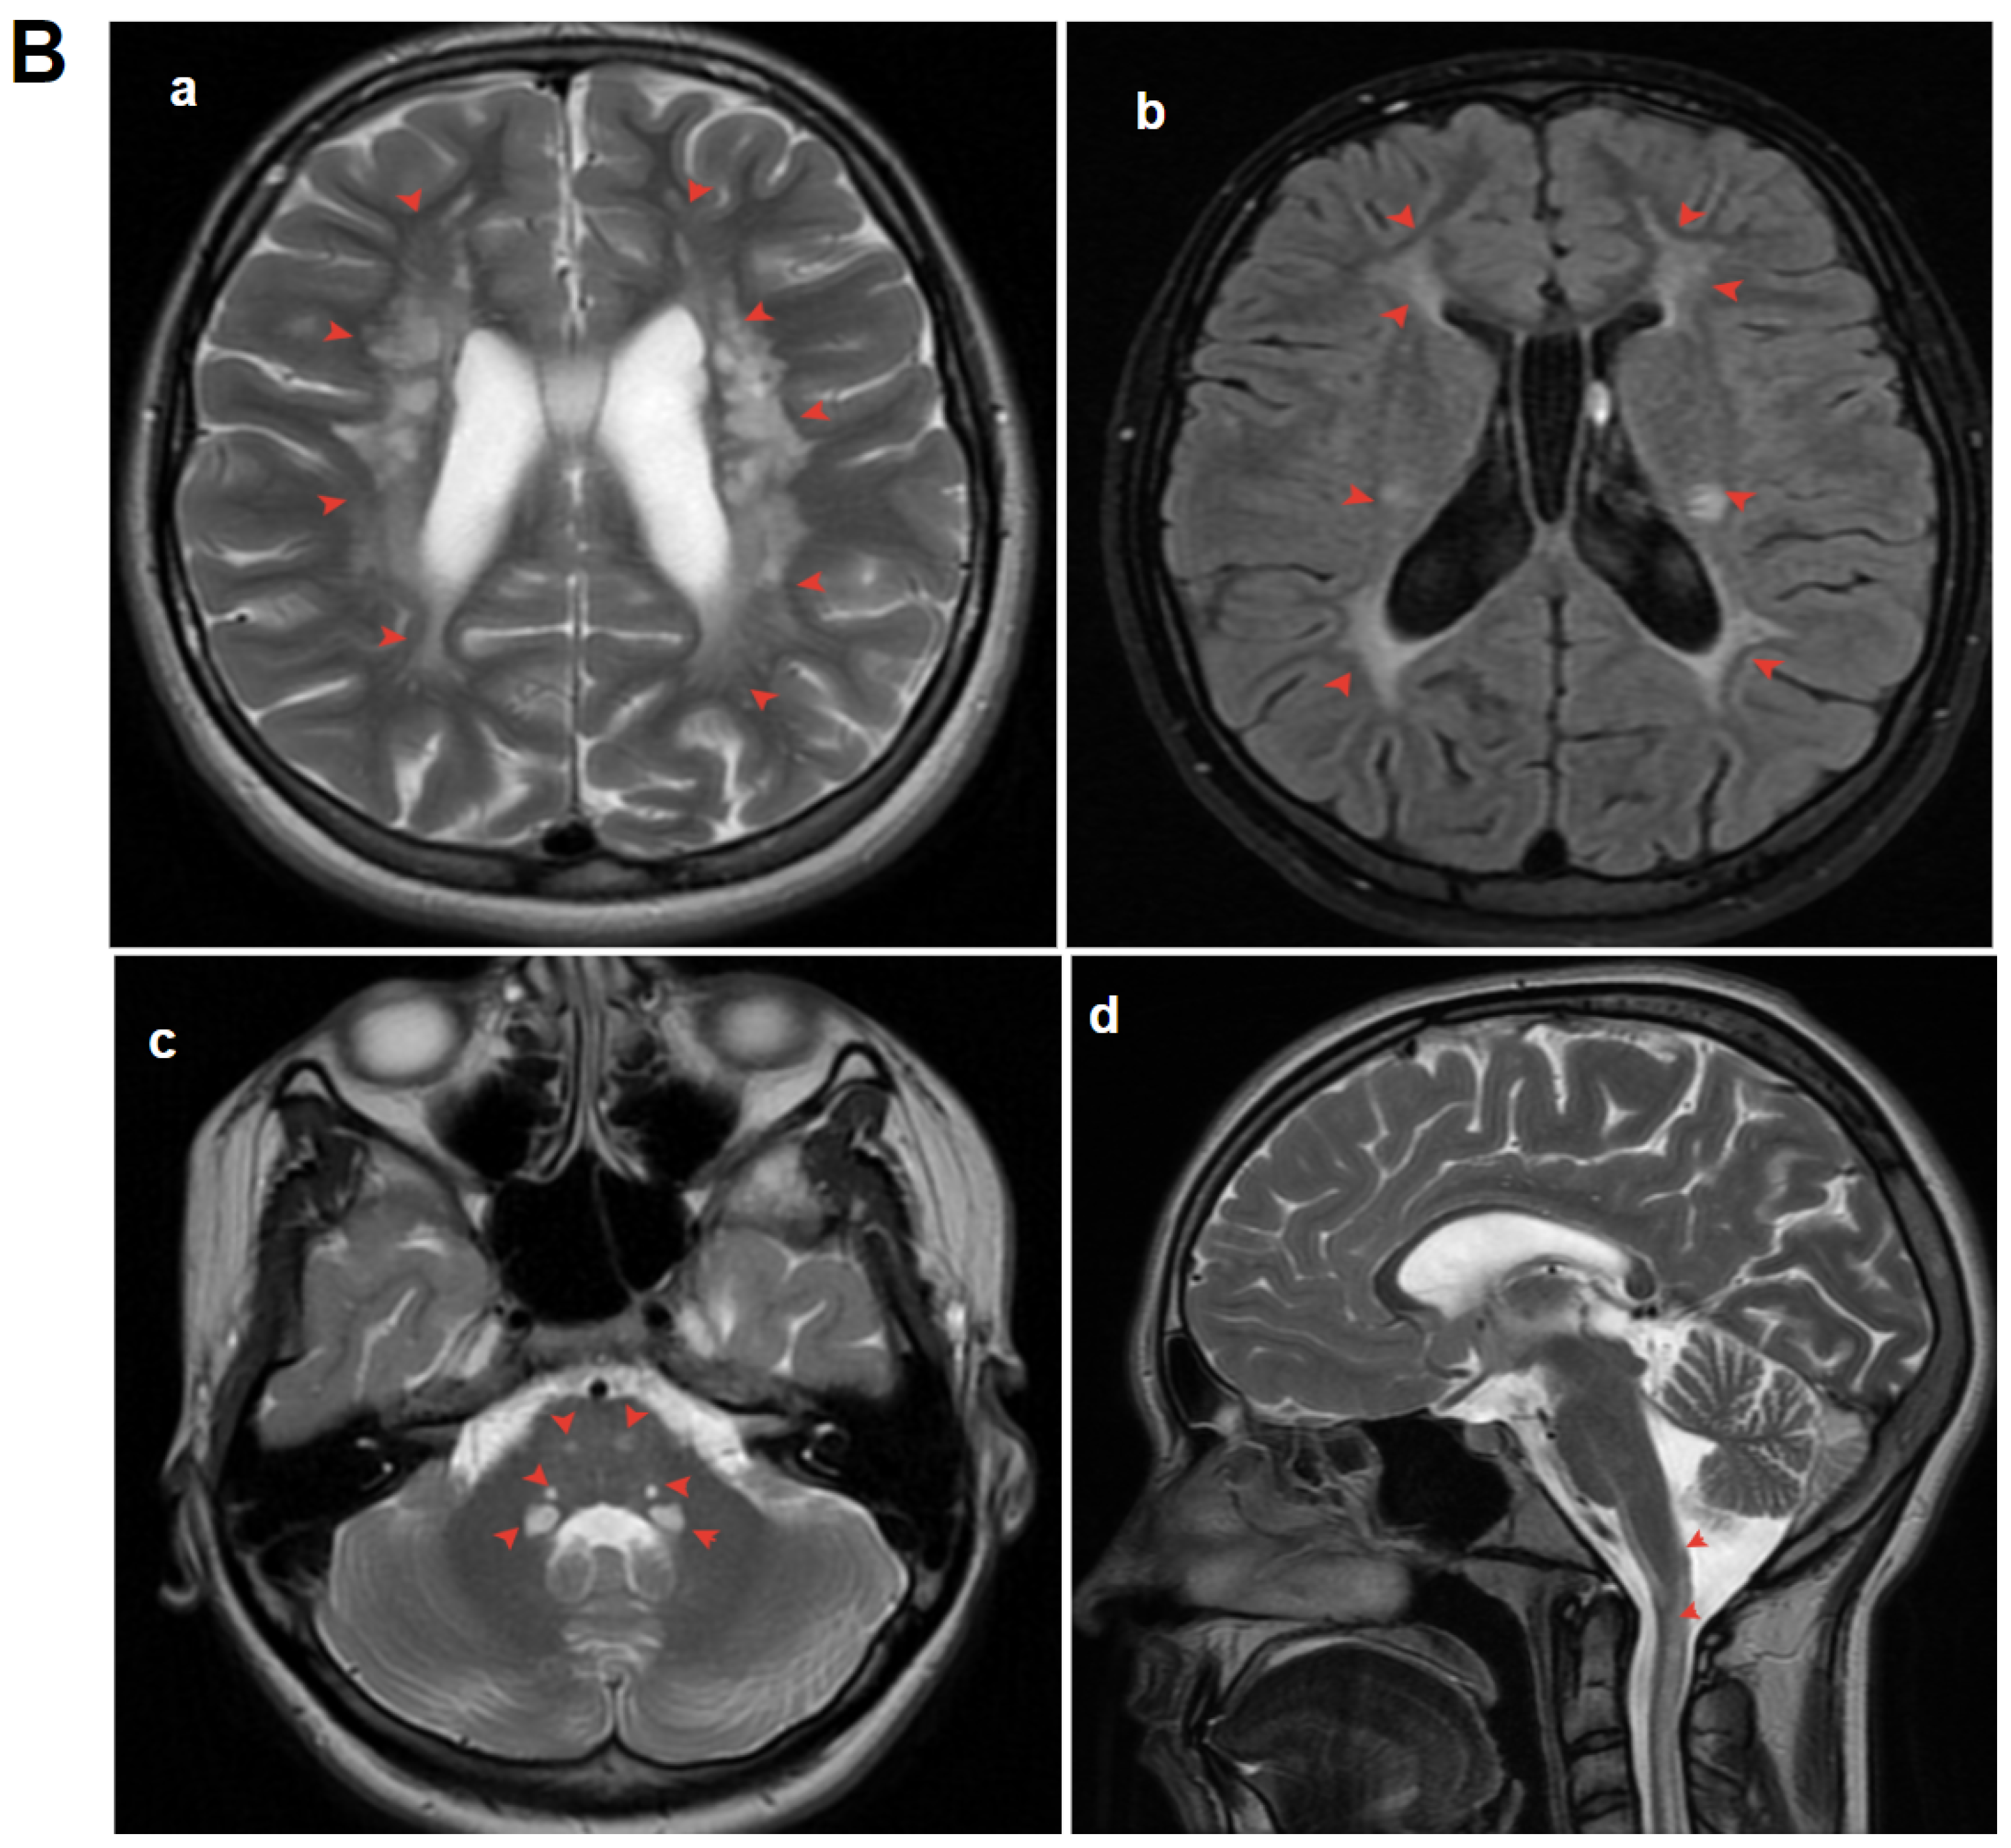

3.1.2. Patient 2